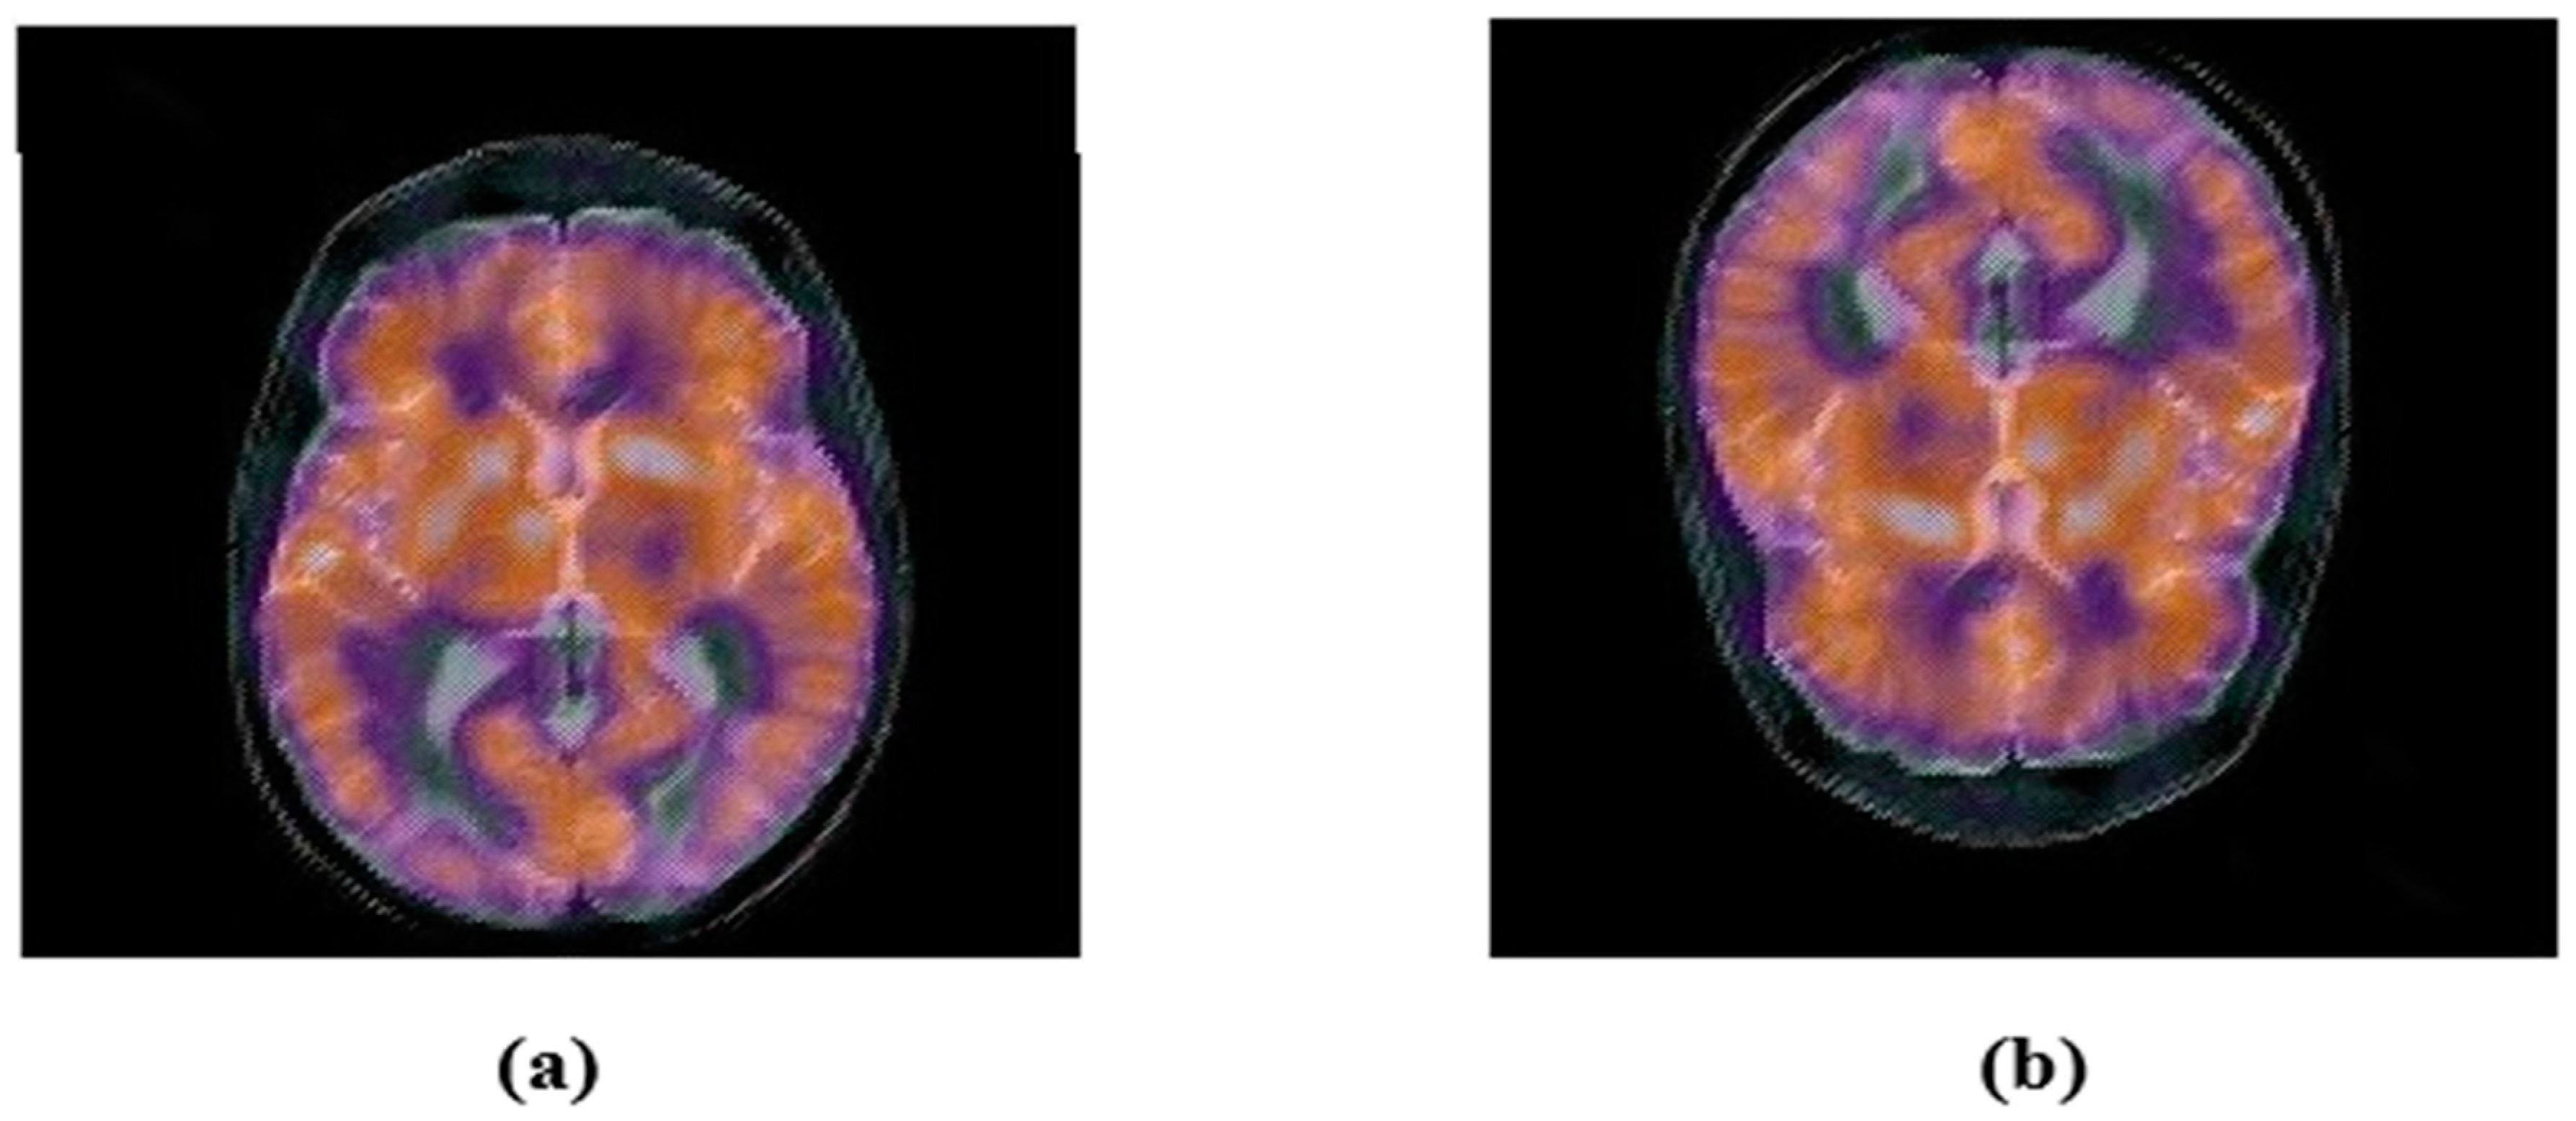

4.2. Robustness

4.2.1. Common Signal Processing Attacks

4.2.2. Geometric Attacks